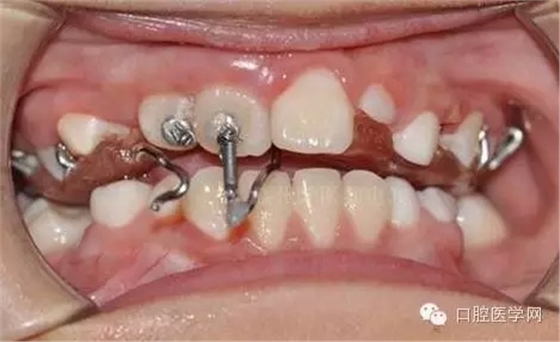

用時9周完成埋伏牙牽引。

孩子自信的微笑,是我們最大的幸福。